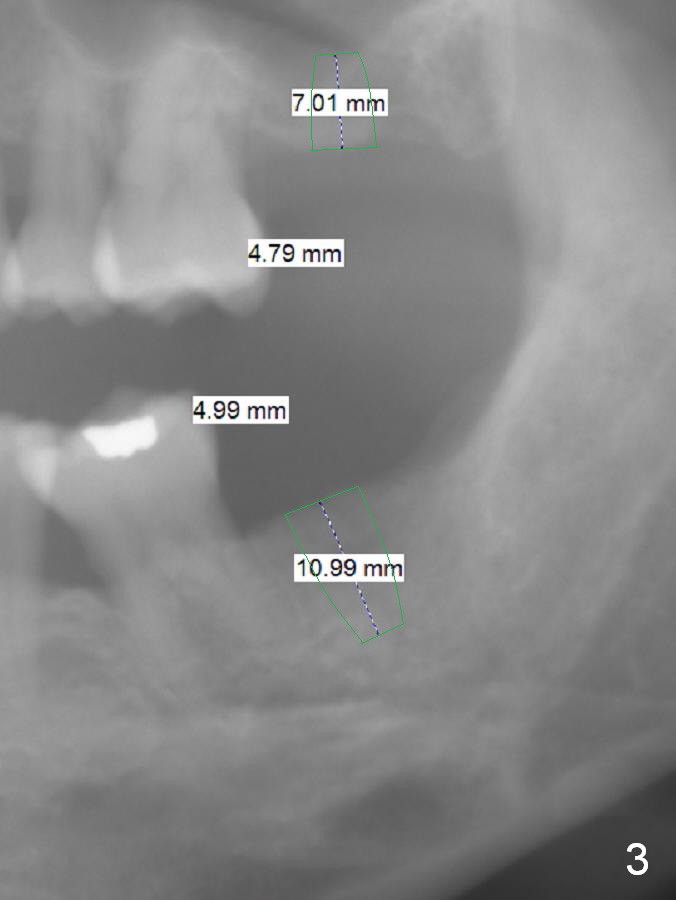

Implants Keep Posterior Vertical Height A 32-year-old woman is concerned about her upper anterior tooth flaring (Fig.1). She is eager for periodontal treatment. She masticates on the right side. The teeth #15 and 18 were extracted ~ 1 year ago. To lessen anterior flaring (take photos when she returns), implants are going to be placed at these sites (Fig.2,3). IBS and Magic Sinus Lift Kits will be used for #15. Magic Split gains access for 5 mm deep (gingival level), followed by ME 3 mm and next ME for 5 mm and Sinus lifter for 9 mm (bone level 7 mm, CMC). Or use the 4.3 mm drill from Magic Sinus Lift Kit for 5 mm, followed by Sinus Lifter for 9 mm. Insert PRF plugs into the sinus, followed by allograft (.5-1.0 mm) with Osteogen. If implant stability is low, place a healing abutment or screw. For #18 implant placement, palpate the ridge to determine the width. Trim the ridge if it is pointed. Also use Magic split for access and bone density testing. Either BEB or PBR will be adopted. The patient is interested in orthodontic treatment. Take Alginate impression and facial photos. Return to Upper Lower Molar Immediate Implant, IBS Xin Wei, DDS, PhD, MS 1st edition 11/15/2016, last revision 01/22/2017 |